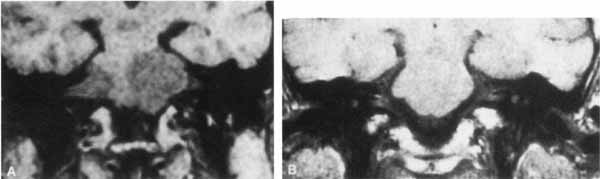

The facial paralysis associated with facial nerve neuromas usually has a gradual onset, but it may be more rapid, simulating idiopathic facial paralysis. Indeed, the pareses may fluctuate or may be associated with hemifacial spasm. In some cases, hearing loss precedes the onset of facial weakness, thereby simulating an acoustic neuroma.93 CT scan typically shows a uniformly enhancing mass in the fallopian canal. T2-weighted MRI images may show a hyperintense mass in the facial canal89 that enhances with gadolinium on T1-weighted images (Fig. 16). The ultimate diagnosis of facial neuroma requires surgical exploration and biopsy. Biopsy usually results in facial paralysis. This possibility should be discussed with the patient before surgery. Facial function recovery after resection of tumor and grafting, although never normal, may include restored tone, symmetry, and weak voluntary movement. The more facial function present before surgery, the better the results with grafting. This observation must be shared with the patient, because he or she might elect to wait until facial function is lost before consenting to surgical removal. When the tumor is located eccentrically, removal is possible with preservation of facial function.94

Fig. 16 Patient with facial neuroma. A. Coronal CT scan demonstrating enlarged stylomastoid foramen and facial nerve mass (arrow). B. Note size of canal in Figure A (black arrow) compared with normal sized canal (open arrow). C. Axial MRI scan showing an enhancing mass of tympanic segment (arrow). D. Coronal gadolinium-enhanced MRI section demonstrating same mass in mastoid segment (arrow).